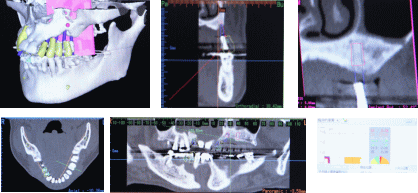

■どのような検査が必要ですか?

検査には、

①お口の中の検査(レントゲン検査、歯周病の検査、かみあわせの検査、口腔内写真など)

②全身的な検査(問診表、血液検査など)

③骨の検査(CT撮影による画像診断→骨の病気の有無や、骨の量や骨質などがわかります)が必要です。